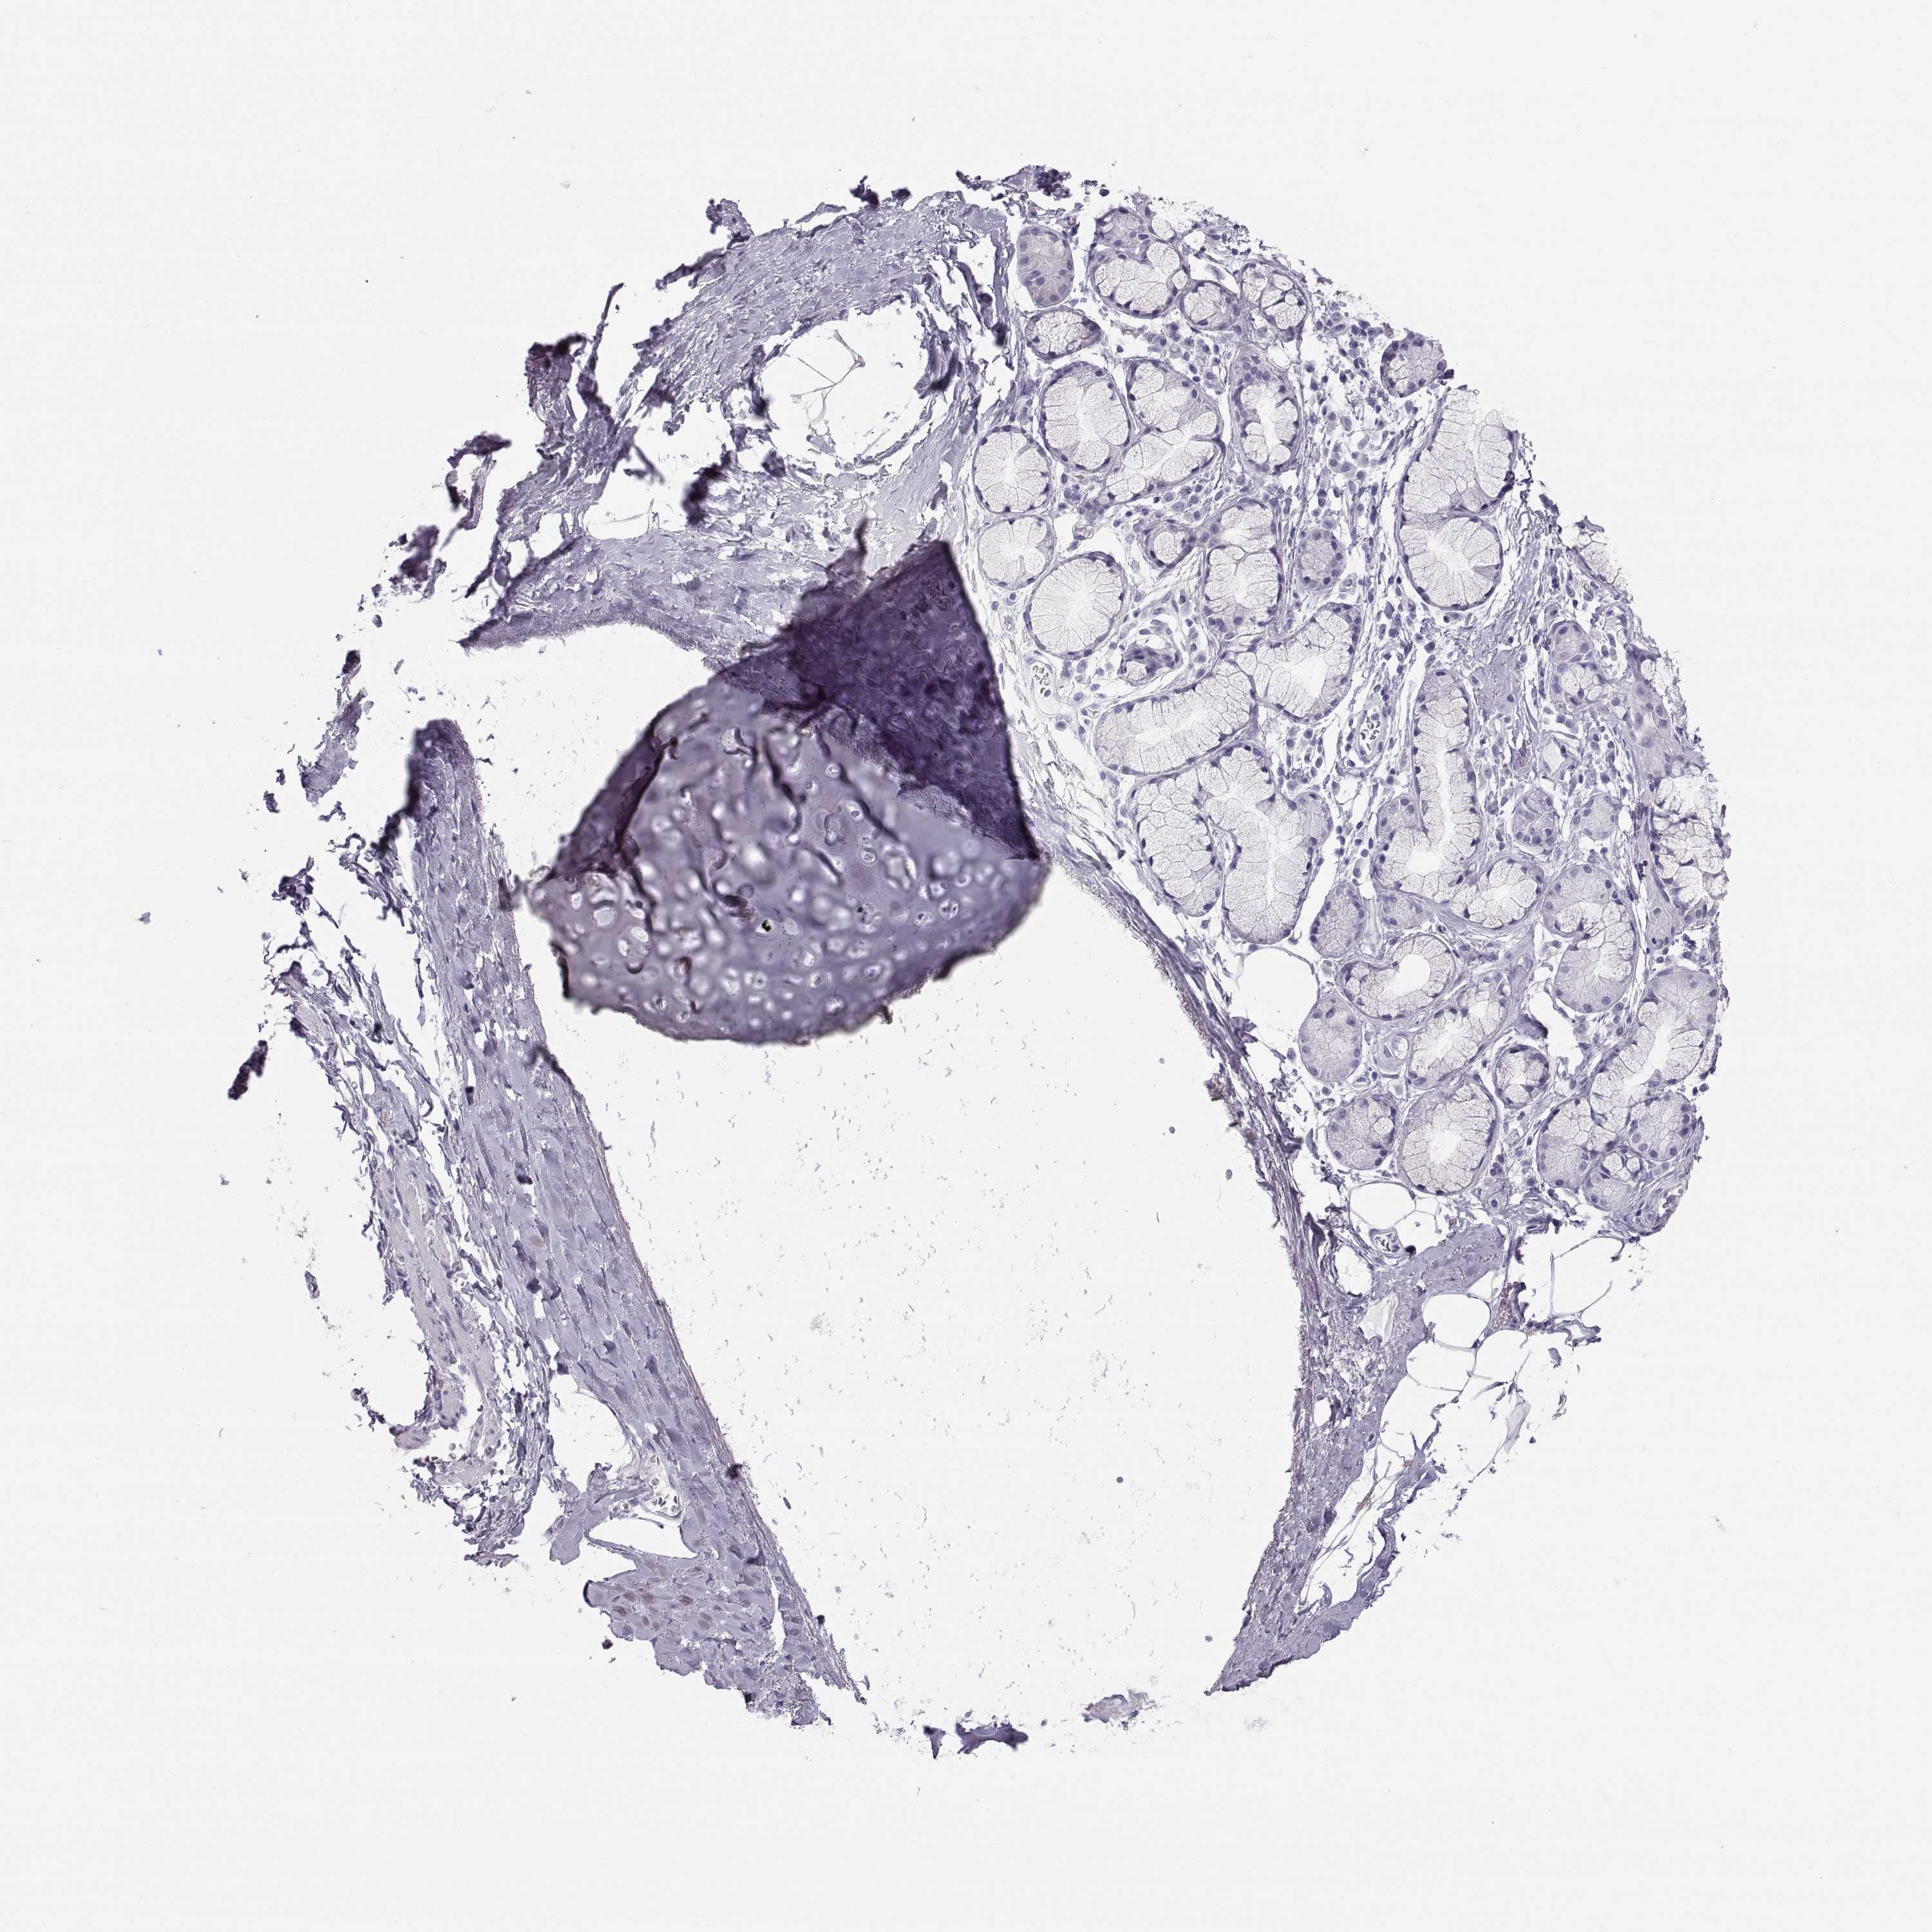

ADIPOSE TISSUE - Antibody stainingi

Antibody staining in the annotated cell types in the current human tissue is reported as not detected, low, medium, or high, based on conventional immunohistochemistry profiling in selected tissues. This score is based on the combination of the staining intensity and fraction of stained cells.

Each image is clickable and will lead to virtual microscopy that enables deeper exploration of all samples and also displays staining intensity scores, fraction scores and subcellular localization as well as patient and tissue information for each sample.

Antibody HPA042476Antibody HPA064892

Adipocytes Not detectedNot detected